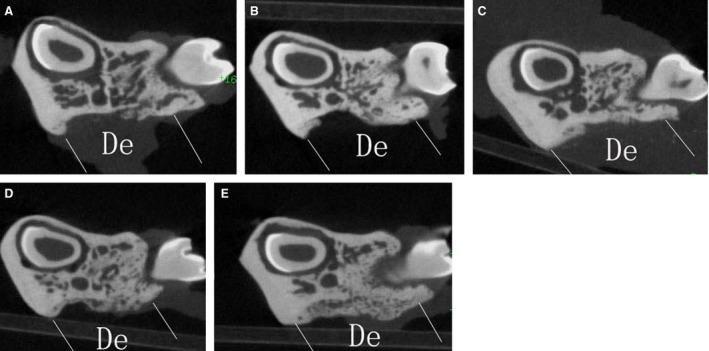

The objective of this study was to investigate the advantages and feasibility of periodontal tissue regeneration using platelet-rich fibrin (PRF) combined with rat periodontal ligament stem cells (PDLSCs) for the first time. We first determined the effect of PRF on rat PDLSCs in vitro. We next conducted an in vivo study, in which a tissue engineering technique was performed to repair periodontal defects in five groups: a blank group, collagen group (implanted collagen membrane), collagen + cells group (implanted collagen membrane and rat PDLSCs), PRF group (implanted PRF membrane) and PRF + cells group (implanted PRF membrane and rat PDLSCs). PRF greatly enhanced cell proliferation, mRNA and protein expression levels of bone sialoprotein (BSP), osteocalcin (OC), and runt-related transcription factor 2 (RUNX2) and activity of alkaline phosphatase (ALP) in vitro. Transplantation of PRF combined with rat PDLSCs resulted in higher expression of osteopontin (Opn), collagen I (COL1A) and RUNX2 at both 12 and 24 days after surgery. Micro-computed tomography and histological analysis showed substantially more new bone formation in the PRF + cells group at 24 days after surgery. Based on these results, we discuss the role of PRF in the proliferation and differentiation of rat PDLSCs and suggest that PRF combined with rat PDLSCs provides a valuable tool for periodontal tissue engineering.

本研究旨在首次探讨富血小板纤维蛋白(PRF)联合大鼠牙周膜干细胞(PDLSCs)用于牙周组织再生的优势和可行性。我们首先确定了 PRF 对大鼠 PDLSCs 的体外作用。然后,我们进行了一项体内研究,采用组织工程技术修复五组牙周缺损:空白组、胶原组(植入胶原膜)、胶原+细胞组(植入胶原膜和大鼠 PDLSCs)、PRF 组(植入 PRF 膜)和 PRF+细胞组(植入 PRF 膜和大鼠 PDLSCs)。PRF 显著促进了细胞增殖,以及骨涎蛋白(BSP)、骨钙素(OC)和 runt 相关转录因子 2(RUNX2)的 mRNA 和蛋白表达水平,以及碱性磷酸酶(ALP)的活性。PRF 联合大鼠 PDLSCs 移植后,术后 12 天和 24 天,骨桥蛋白(Opn)、Ⅰ型胶原(COL1A)和 RUNX2 的表达水平更高。微计算机断层扫描和组织学分析显示,术后 24 天 PRF+细胞组有更多的新骨形成。基于这些结果,我们讨论了 PRF 在大鼠 PDLSCs 增殖和分化中的作用,并提出 PRF 联合大鼠 PDLSCs 为牙周组织工程提供了有价值的工具。